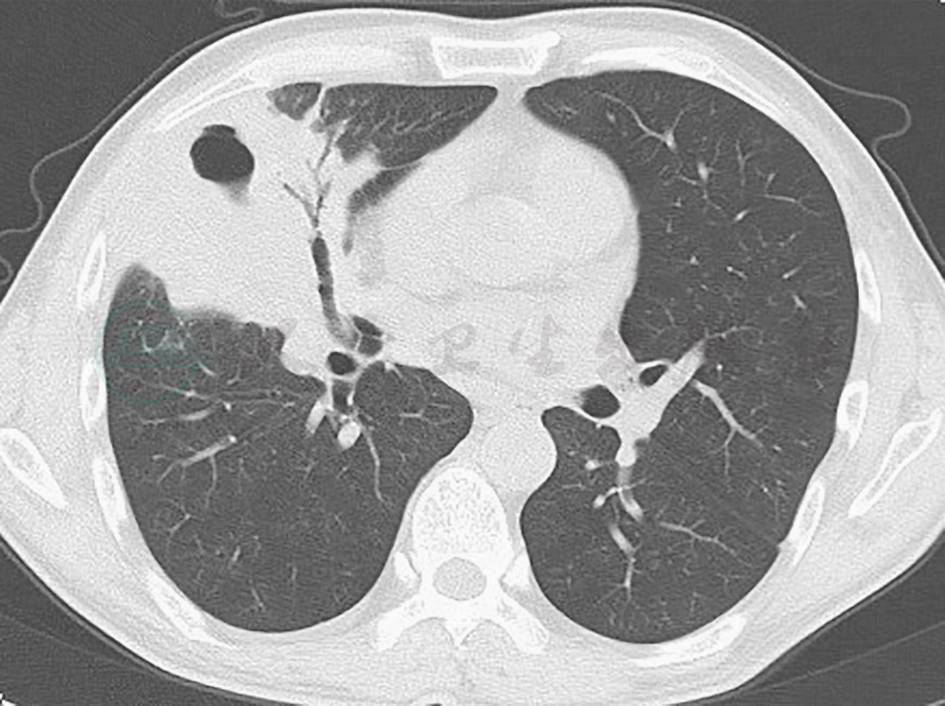

真菌感染:本例患者外观消瘦,曾在外院接受广谱抗生素治疗,需注意念珠菌二重感染可能(念珠菌性肺炎可表现为肺实变影),需积极寻找病原学依据以助鉴别。另外,曲霉菌感染常继发于免疫功能低下的情况,病情进展迅速且凶险,其典型胸部影像学表现为晕征和新月征(图2),与本例患者情况不符,可基本排除。

图2 肺曲霉菌病胸部影像学表现

胸部CT可见右上肺肿块样高密度影,伴支气管充气征